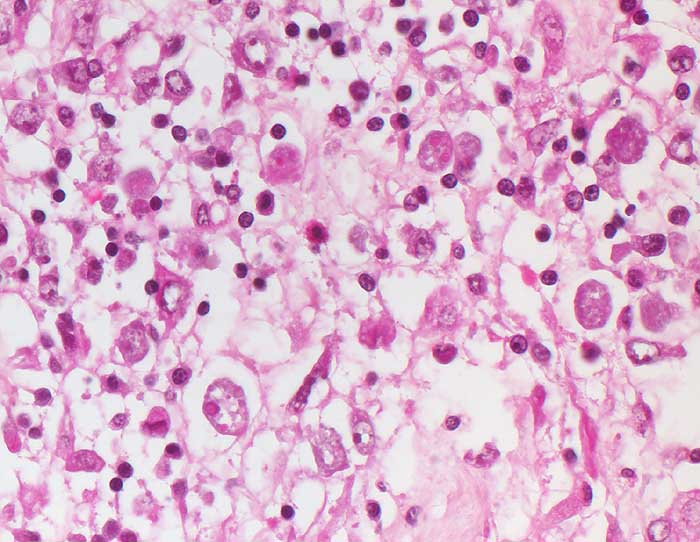

Amöbenkolitis

Entzündung infektiös

Kolon